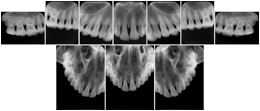

3. A dental provider wishes to capture a series of DICOM IO images for the patient’s dentition. The tooth morphology, teeth are divided into molars, premolars, canines and incisors, and a number of images for each jaw. The anatomic information was captured utilizing the triplet of schema. This standard code sequence is based on ISO 3950-2010, Dentistry - Designation system for teeth and areas of the oral cavity.

Every IO image should have anatomic information either through the primary or modifier sequence.

In most standard cases, images are oriented in structured layouts. These structured displays are useful to be shared between providers for reference purposes.

Table OO.1.1-1 shows structured display standard templates, where Viewset ID is based on the Japanese Society for Oral and Maxillofacial Radiology (JSOMR) classification provided by JIRA (Japan Medical Imaging and Radiological Systems Industries Association, www.jira-net.or.jp). Expected or typical teeth to be imaged location, region and designation codes are based on ISO 3950-2010, Dentistry - Designation system for teeth and areas of the oral cavity. For all the hanging protocols listed in OO.1.1-1, the value to use for Hanging Protocol Creator (0072,0008) is "JSOMR" and the value to use for Hanging Protocol Name (0072,0002) does not include "JSOMR" (e.g., "DL-S001A", not "JSOMR DL-S001A").

Table OO.1.1-1. Hanging Protocol Names for Dental Image Layout based on JSOMR classification